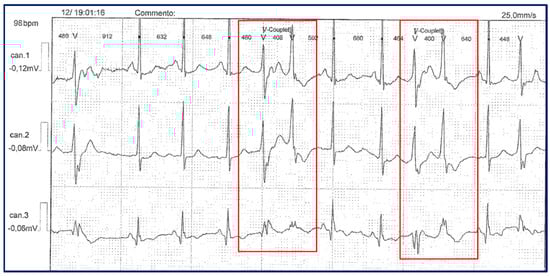

| Our Family Case | Uncle | 34/M | Cramps, myalgias, muscle weakness | General muscle hypertrophy | 4.2 | 297 | Coronary artery by-pass graftings; IHD; sVT; sEVB; EVB | 360 | --- | Metabolic syndrome | 66 |

| Father | 6/M | Cramps, myalgias post-exercise | Lower limbs | 5.4 | 827 | AMI; eccentric hypertrophy of LV; ICD implant sVT; nsVT | 450 | Dental crowding | Metabolic syndrome; OSA | 68 | |

| Cousin | 24/F | Cramps; muscle weakness; myotonia | Lower limbs | 3.9 | 171 | Normal | 370 | Small ears | 5 | ||

| Older brother | 12/M | Cramps; muscle stiffness at lower limbs | Lower limbs | 4.7 | 150 | Sinus arrhythmia; decreased amplitude of T waves in LPL | 380 | Jaw hypoplasia; dental crowding; clinodactyly fifth toe; syndactyly of II/III fingers of hands | Obesity | 39 | |

| Proband | 16/F | Premenstrual episodes of PP, muscle stiffness | Upper and lower limbs | 4.4 | 97 | Sinus Bradycardia; EVB during FU | 370 | Micrognathia, elusive chin, low set of ears, dental crowding, hypotelorism, mall hands/ feet | ___ | 37 | |

| Young brother | 11/M | Muscle stiffness | Upper limbs | 4.9 | 426 | Sinus Bradycardia; transient WPM | 370 | Scoliosis, micrognathia, small ears, hypertelorism, short neck, fingers clinodactyly and syndactyly | Obesity | 32 | |